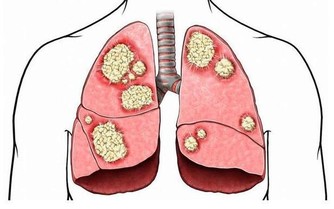

6.久治不愈的乾咳或痰中帶血,可見於肺癌。

CT(電子計算機斷層照相術):相對於B超和X線檢查有更高的精度,更利於早期發現病灶,有助於早期診斷。

MRI(核磁共振成像):對於軟組織的分辨強於CT,對於神經系統疾病,顱內、脊髓腫瘤診斷比較準確,了解腫瘤與血管關係及腫瘤範圍。對腫瘤早期生化代謝改變測定有利於腫瘤的早期診斷。

PET-CT(正電子發射型計算機斷層掃描):腫瘤組織一把具有比正常組織更強的代謝能力,根據代謝能力進行檢查,發現可疑病灶。